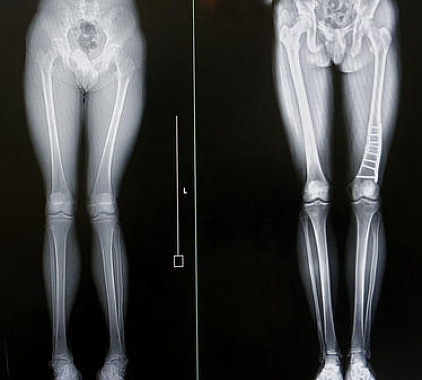

Фотогалерея